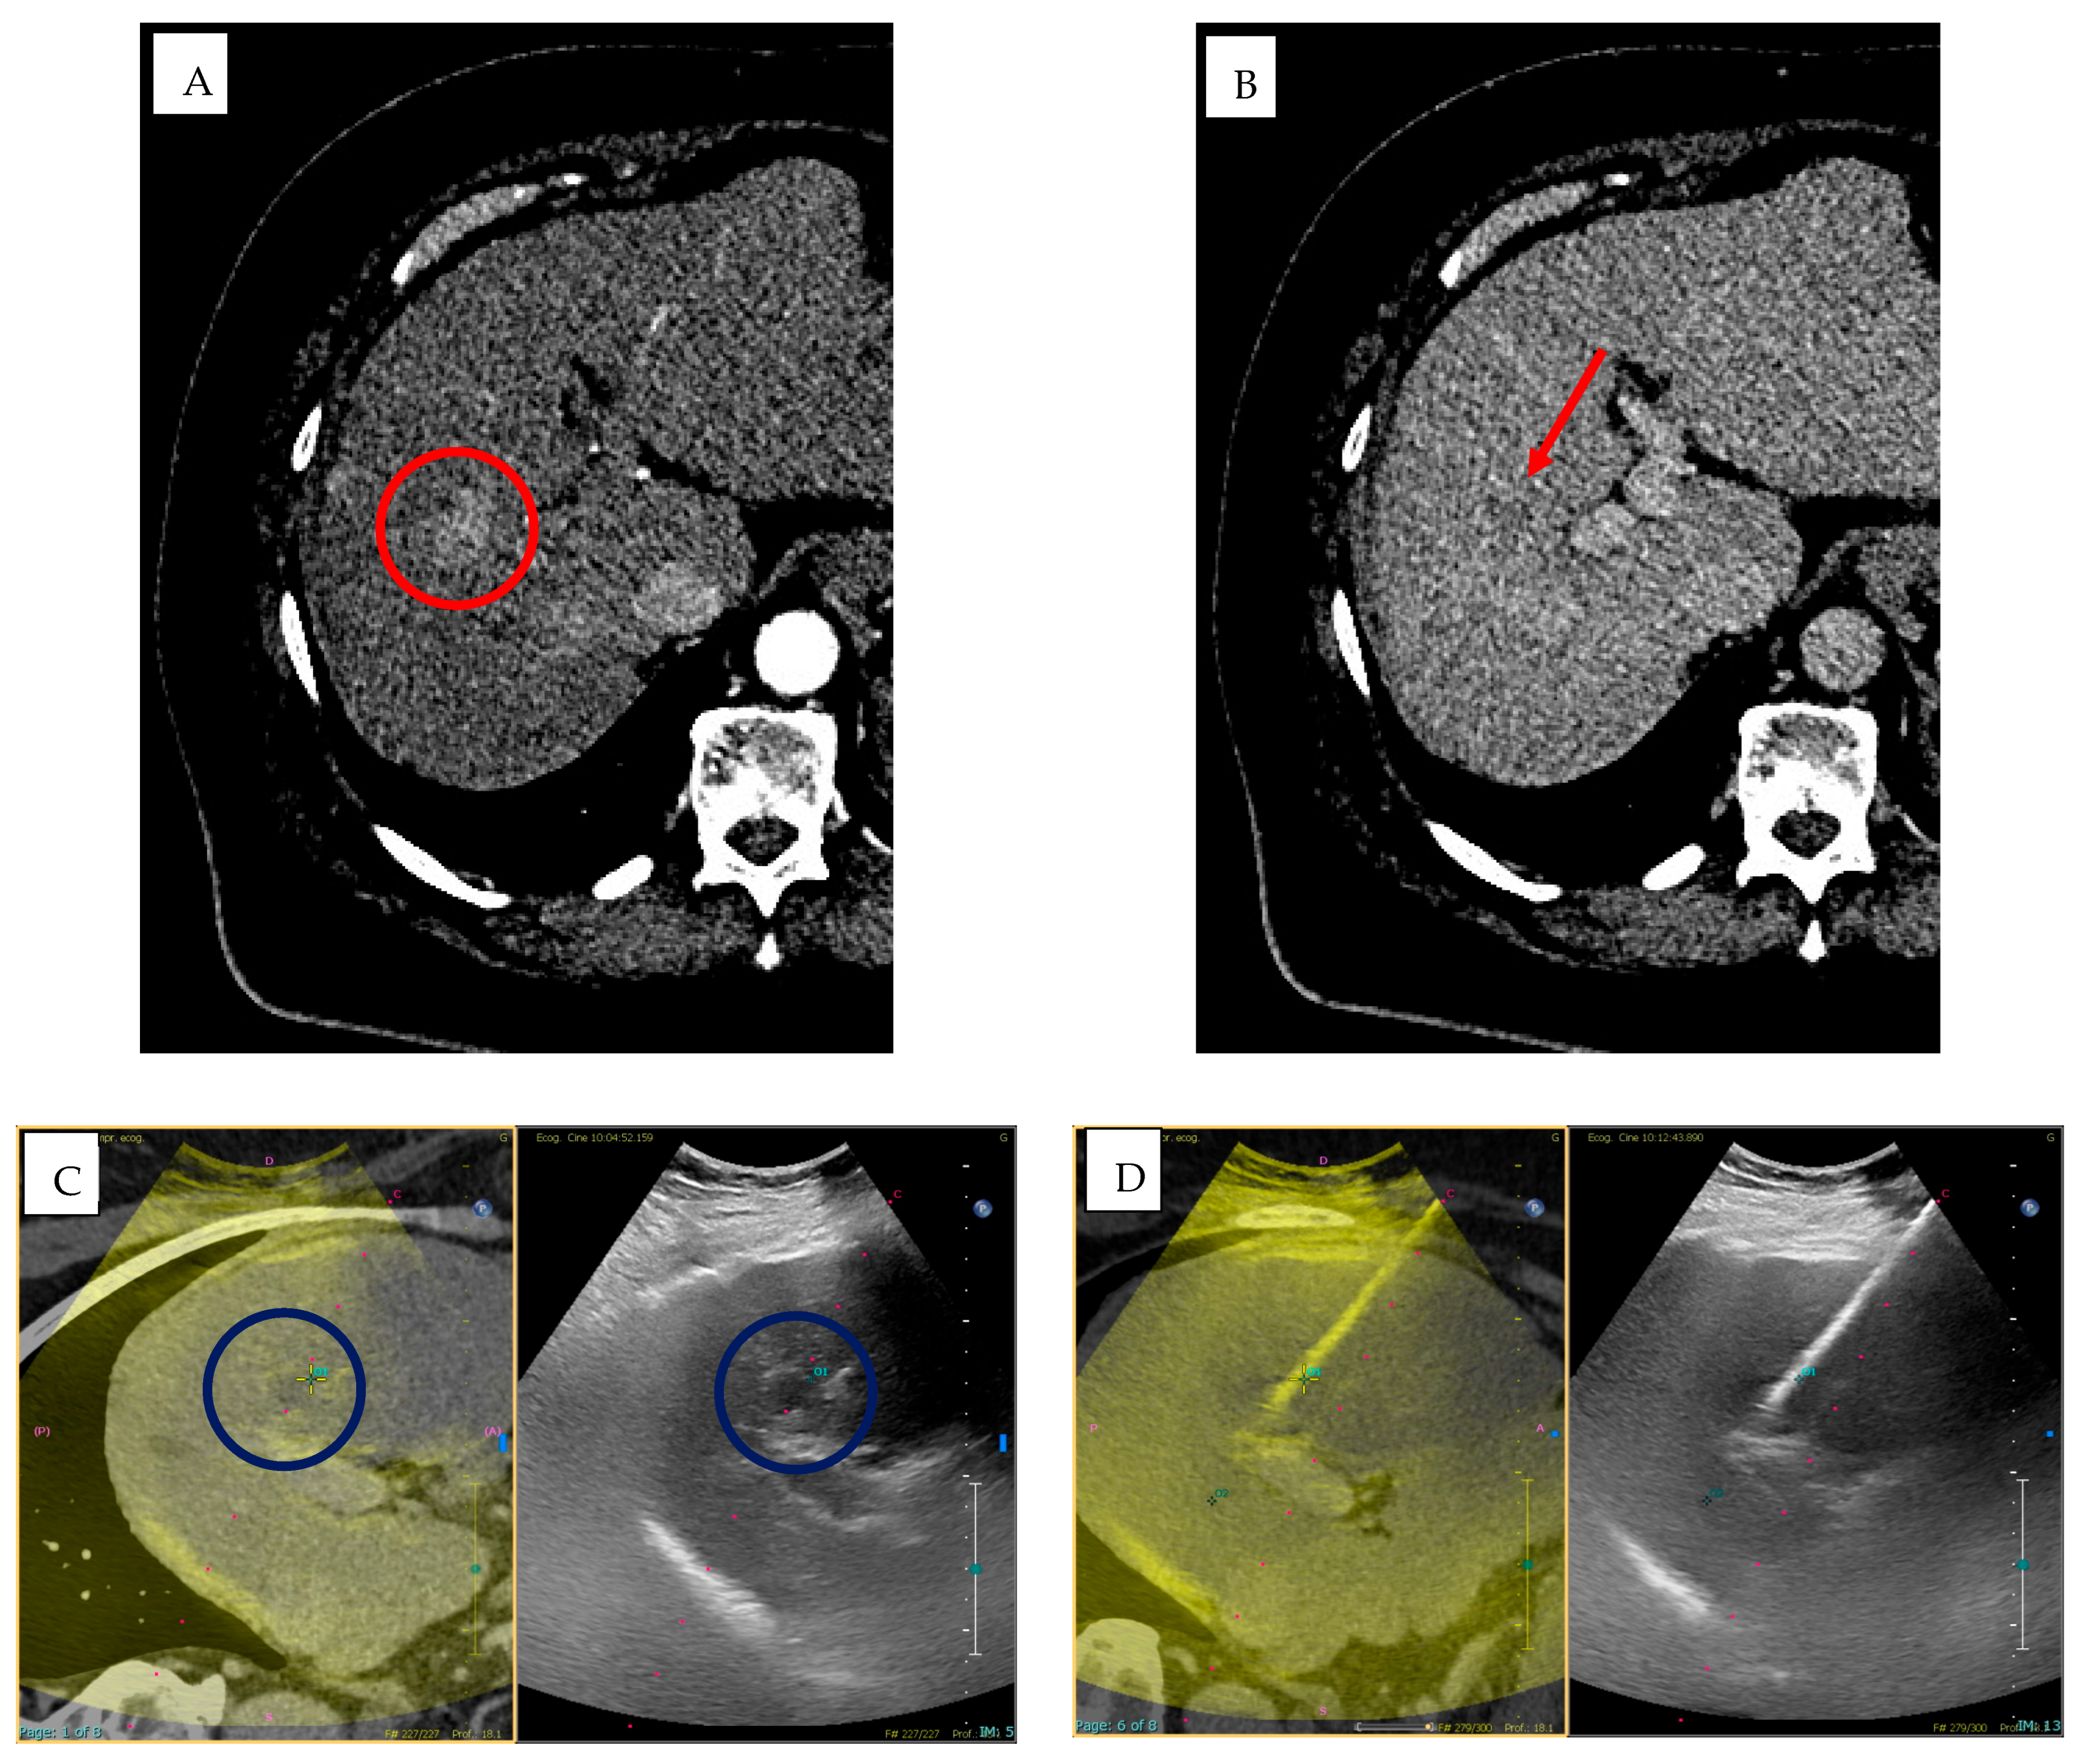

- Biondetti, P.; Ierardi, A.M.; Casiraghi, E.; Caruso, A.; Grillo, P.; Carriero, S.; Lanza, C.; Angileri, S.A.; Sangiovanni, A.; Iavarone, M.; et al. Clinical Impact of a Protocol Involving Cone-Beam CT (CBCT), Fusion Imaging and Ablation Volume Prediction in Percutaneous Image-Guided Microwave Ablation in Patients with Hepatocellular Carcinoma Unsuitable for Standard Ultrasound (US) Guidance. J. Clin. Med. 2023, 12, 7598. [Google Scholar] [CrossRef]

- Monfardini, L.; Orsi, F.; Caserta, R.; Sallemi, C.; Della Vigna, P.; Bonomo, G.; Varano, G.; Solbiati, L.; Mauri, G. Ultrasound and cone beam CT fusion for liver ablation: Technical note. Int. J. Hyperth. 2018, 35, 500–504. [Google Scholar] [CrossRef]